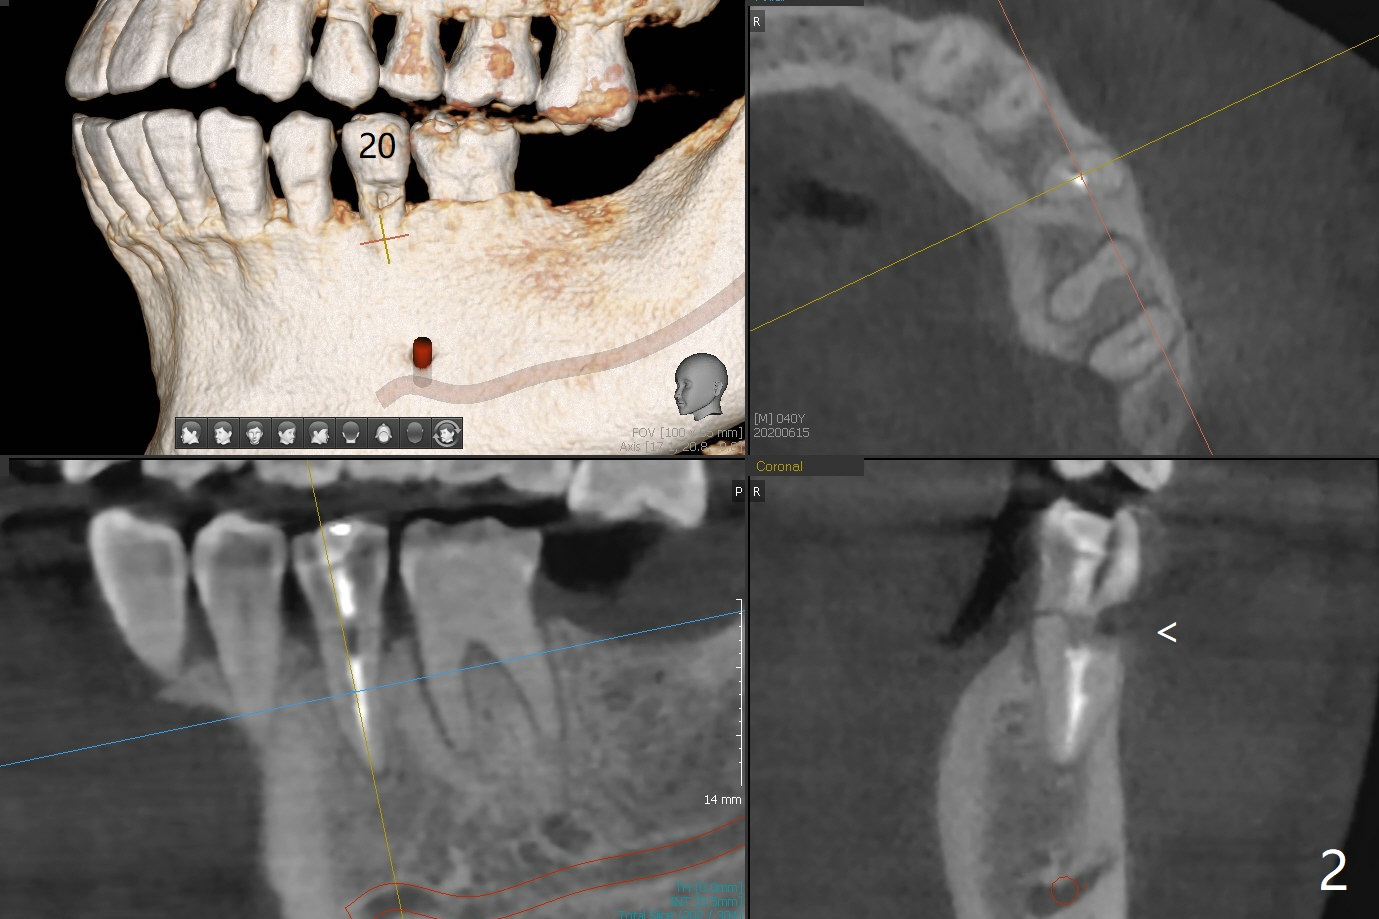

A 40-year-old man with #18 missing and #31 residual roots just fractures the tooth #20 (Fig.1). After discussion, he agrees to have implants at #18 and 20 first. To prevent buccal drifting of osteotomy and implant at #20, the implant will be placed lingual, but it does not contact the lingual plate (Fig.2-4). Traditionally, the whole tooth needs to be extracted (Fig.5,6) before initial osteotomy (Fig.7 red). The latter has tendency to drift buccal because of the lingual slope (Fig.7 arrow). To prevent the drifting, the crown of the tooth is removed (Fig.8). A guide is fabricated with 12 mm offset so that after bone trimmer (Fig.9 pink), the following drills have more contact with metal sleeve. Furthermore the drills will have less chance of buccal shifting because of the presence of the root.